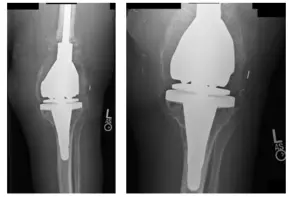

Patient came in with X-rays to review, as shown below. Upon examination, patient was experiencing pain and was ultimately advised to receive a left staged Total Knee Arthroplasty (TKA) Reconstruction surgery. All alternatives and options were discussed at length with the patient.

X-Rays show osteolysis of the femoral and tibial component of the left TKA prosthesis

There is also capsular calcification and capsular distention along with severe thinning of the cortex around the upper aspect of the femur. Arrows show osteolysis of the bone.